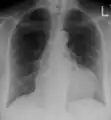

Ultrasounds showing a pericardial effusion in someone with pericarditis

A pericardial effusion as seen on CXR in someone with pericarditis

The diagnosis of tamponade can be confirmed with trans-thoracic echocardiography (TTE), which should show a large pericardial effusion and diastolic collapse of the right ventricle and right atrium. Chest X-ray usually shows an enlarged cardiac silhouette ("water bottle" appearance) and clear lungs. Pulmonary congestion is typically not seen because equalization of diastolic pressures constrains the pulmonary capillary wedge pressure to the intra-pericardial pressure (and all other diastolic pressures).